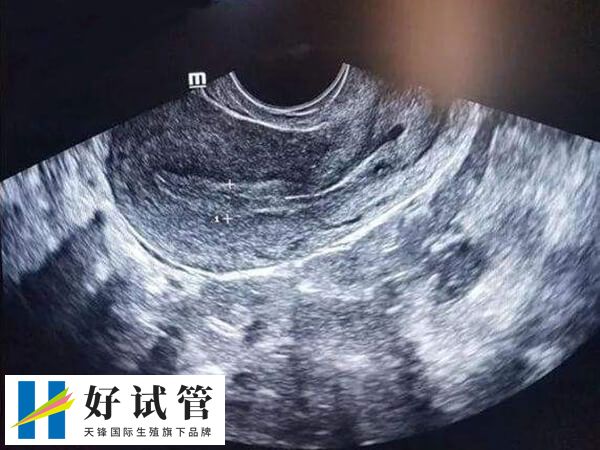

宫颈息肉是由于宫颈长期慢性炎症刺激宫颈的黏膜,引起增生,而子宫有一种天然的排除异物的能力,使增生的子宫颈黏膜逐渐自基底部向宫颈外口突出形成息肉。

息肉一般呈赤色,舌状,非常柔软,容易触及出血,同时宫颈息肉还有一个根部 ,称为蒂,一般蒂细长,大多附着子宫颈外口。有时几个息肉可同时生长,发生率约为5%,占悉数宫颈病变的4%-10%。